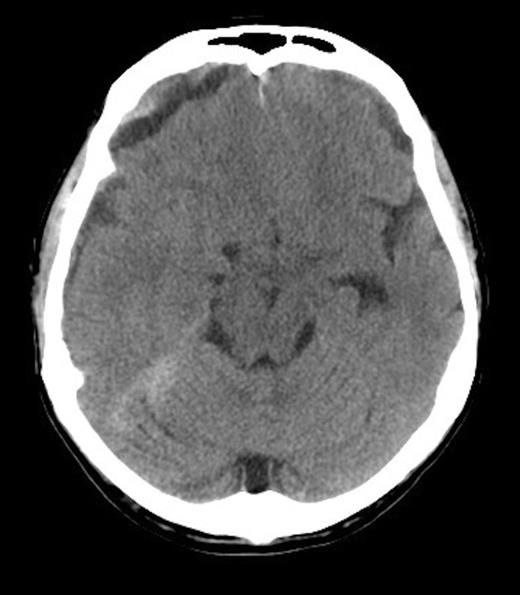

A 62-year old male presented to the emergency department of our institution with epistaxis, anaemia (Hb: 48g/L) and thrombocytopenia (platelets: 52x109/L). Past history included a diagnosis of metastatic prostate adenocarcinoma 7 years earlier. He denied headaches and there were no neurological deficits other than mild cognitive impairment. He was noted to be coagulopathic with an INR of 1.5, despite platelet, fresh frozen plasma and red blood cell transfusion, his coagulopathy ultimately worsened. His level of consciousness deteriorated and a CT Brain was performed identifying acute on chronic SDH (Figure 1 & 2).